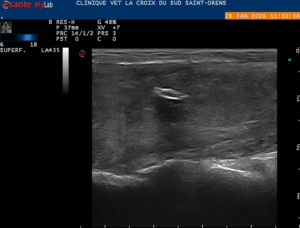

Affection touchant quasi exclusivement le chien, la migration de corps étrangers de type épillets peut provoquer des abcès profonds, dont la localisation peut être problématique. Fréquemment ces corps étrangers peuvent provoquer des abcès pulmonaires, des pyothorax (infection thoracique), des abcès sous-lombaires (avec infection vertébrale), etc…

Grâce au scanner qui améliore beaucoup la précision de la recherche du corps étranger, nous pratiquons de nombreuses interventions sur ces abcès profonds. Les corps étrangers sont localisés en cours de chirurgie grâce à de l’échographie per-opératoire, permettant de réduire les risques et le délabrement musculaire.